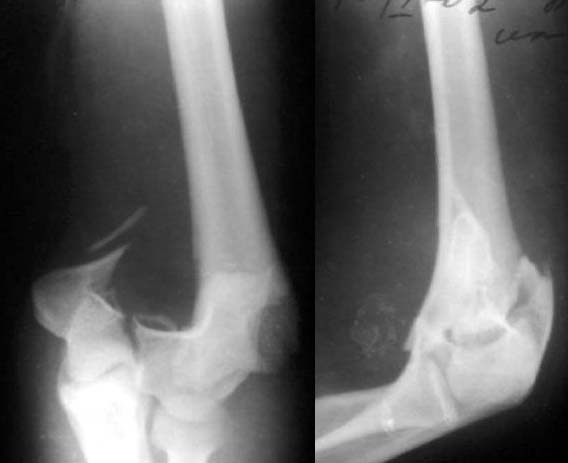

Женщина, 37 лет. Травма в результате падения на улице. Закрытый многооскольчатый перелом дистального метаэпифиза левой плечевой кости со смещением. Неврологических и сосудистых нарушений не выявлено.Лечение? Если внешняя фиксация, то - каков монтаж АВФ? Сейчас пациентка на скелетном вытяжении.С уважением,А.В.Владзимирский

До лечения

Лечение тут, видимо, должно основываться в первую очередь на открытой репозиции, поскольку возможности закрытой при таких повреждениях далеко недостаточны. Если поверхность блока состоит не просто из двух крупных фрагментов, лучше идти с отсечением локтевого отростка. Вопрос о методе фиксации более второстепенный. Можно и аппаратом. В приложении - пример лечения такого повреждения с внутренней фиксацией.